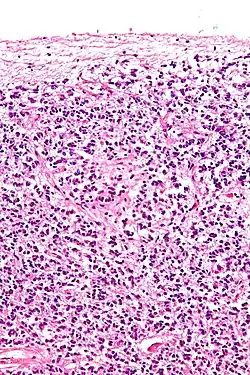

![]() Cross-section of pineal gland displaying pinealocytes and other cells | |